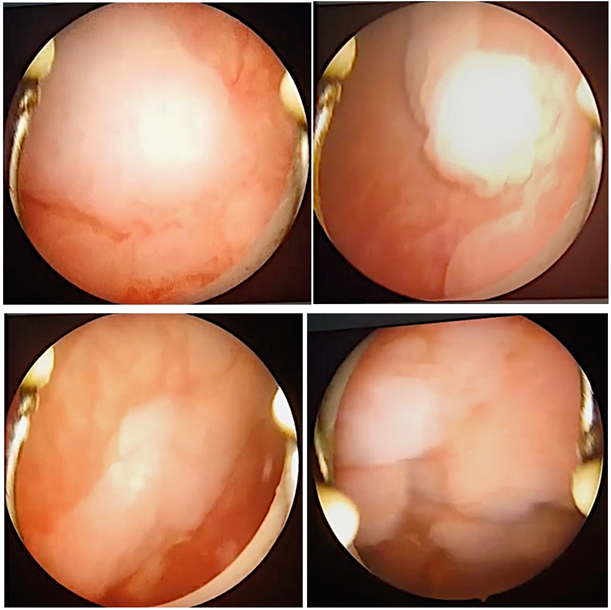

She presented for further resection of bladder lesions (Figure 1).

Figure 1: Condylomas affecting all bladder walls.